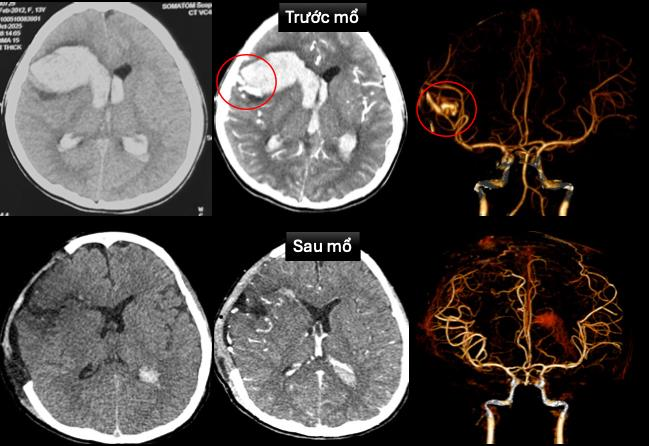

- Bệnh sử: sáng cùng ngày nhập viện, bệnh nhân đang ngủ, thở ngước, hôn mê được người nhà đưa vào bệnh viện Hóc Môn. Chẩn đoán hôn mê nghi do xuất huyết não, sốc tim được đặt nội khí quản và sử dụng thuốc vận mạch, chuyển bệnh viện Nhi Đồng 1. Tại khoa cấp cứu, bệnh nhân được ghi nhận tình trạng hôn mê sâu, thở máy qua nội khí quản, nhịp chậm, huyết áp thấp đang duy trì thuốc vận mạch. Bệnh nhân được siêu âm tim, chụp cắt lớp vi tính sọ não dựng hình mạch máu não cấp cứu. Chẩn đoán: dị dạng động tĩnh mạch trán phải vỡ gây xuất huyết nhu mô não lan vào hệ thống não thất, sốc tim, rối loạn nhịp, bệnh cơ tim xốp. Bệnh nhân được hội chẩn đa chuyên khoa, tiến hành can thiệp cấp cứu. Bs tim mạch can thiệp đặt máy tạo nhịp tạm thời. Bs ngoại thần kinh phẫu thuật cấp cứu mở sọ giải áp, vi phẫu cắt dị dạng mạch máu não, lấy máu tụ trong nhu nhô não và não thất. Sau mổ, bệnh nhân được chuyển khoa hồi sức ngoại điều trị hồi sức tích cực, thông khí cơ học, sử dụng thuốc vận mạch, chống phù não. Tình trạng bệnh nhân ổn định dần, hiện tại đã tỉnh táo, còn yếu nhẹ chân phải, tình trạng tim mạch ổn định đã rút được máy tạo nhịp và ngưng thuốc vận mạch. Hình ảnh chụp cắt lớp vi tính sọ não sau mổ không còn ghi nhận dị dạng mạch máu não. Siêu âm tim kiểm tra: ghi nhận bệnh cơ tim xốp với tình trạng chức năng co bóp cơ tim cải thiện (EF 65%).

Hình 1: Hình ảnh chụp cắt lớp vi tính sọ não và dựng hình mạch máu não trước và sau mổ